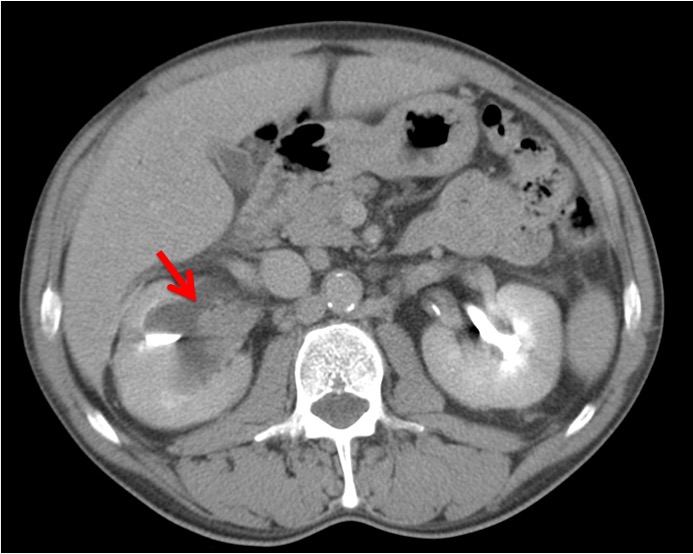

Paciente de 59 años con antecedentes personales de Cá de vejiga.

Se le realiza una Uro-Tc por seguimiento al año, aunque en esta ocasión el paciente refiere episodio de hematuria.

Tras el tratamiento de la recidiva y nefrostomía para la hidroureteronefrosis, vuelve acudir al hospital a los 9 meses por episodio de dolor en FD y malestar general. Se realiza una ecografía de urgencias.

Se realiza nueva TC bifásico abdominopélvio y Uro TC.

- Paciente con numerosas recidivas por Cá vejiga.

- Ha desarrollado un tumor metacrónico en pelvis renal derecha, también responsable de la hidroureteronefrosis.

- Mala evolución radiológica del proceso a expensas de metástasis pulmonares y hepáticas.